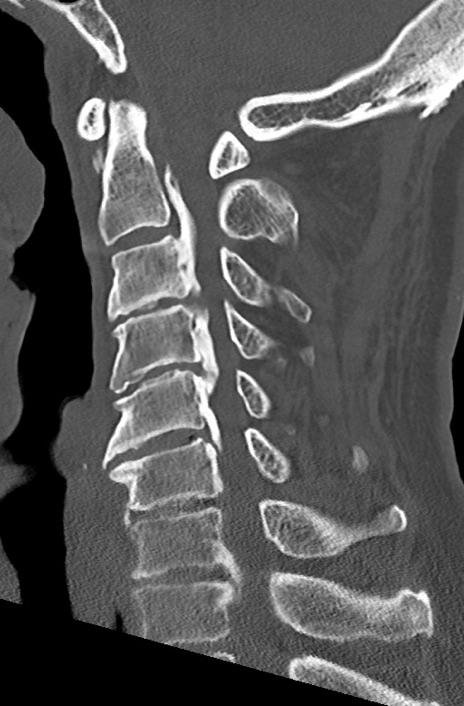

【整形】TIPS症例7 頚椎CT(矢状断像)

頚椎CT

矢状断像と横断像